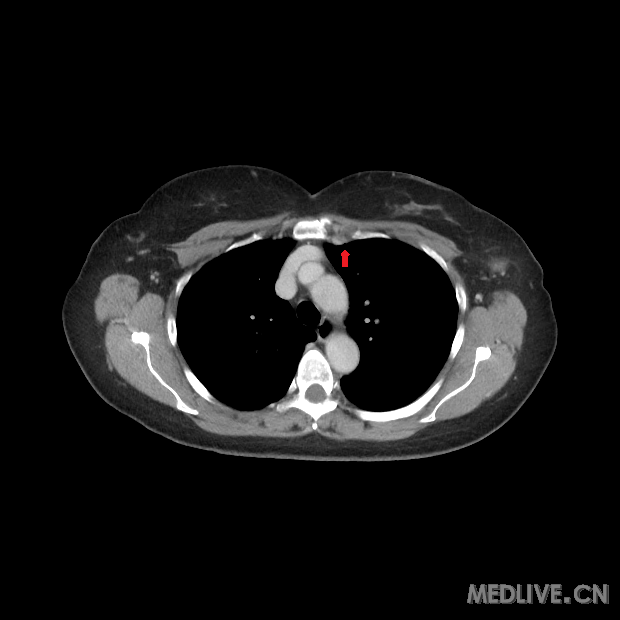

非霍奇金淋巴瘤影像-医学影像图,_医学图库